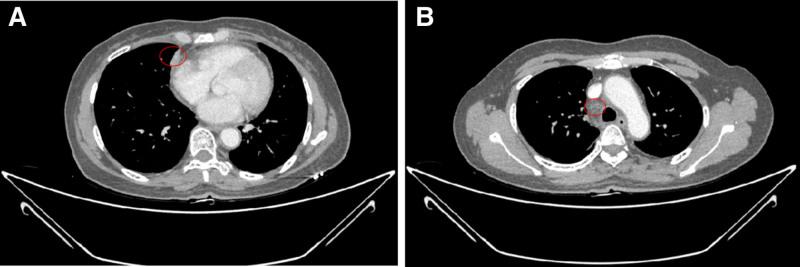

The patient initially received first-line treatment with pembrolizumab combined with docetaxel and nedaplatin, achieving partial response. After progression, second-line therapy included gemcitabine and cisplatin chemotherapy with synchronous radiotherapy, followed by camrelizumab and anlotinib. Regular imaging follow-ups guided therapy adjustments, including extended dosing intervals for camrelizumab during disease stabilization.

Over 4 years of treatment, the patient achieved durable partial response, with significant reduction in tumor burden and no new metastases. As of the most recent follow-up, the patient exhibited an overall survival of 59 months and progression-free survival of 51 months for second-line therapy, with manageable adverse effects including secondary hypothyroidism and grade 2 hypertension.

患者最初接受帕博利珠单抗联合多西他赛和奈达铂的一线治疗,达到部分缓解。进展后,二线治疗包括吉西他滨和顺铂化疗同步放疗,随后是卡瑞利珠单抗和安罗替尼。定期影像学随访指导治疗调整,包括在疾病稳定期间延长卡瑞利珠单抗的给药间隔。

结果